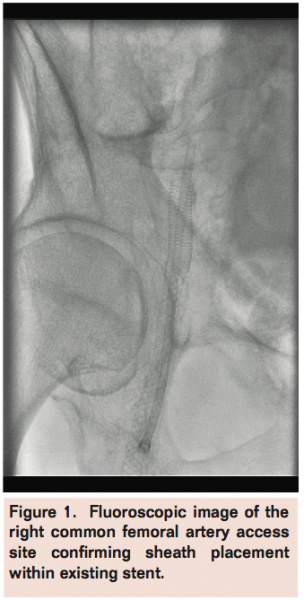

The patient was seen in follow up 4 months later and findings from duplex arterial Doppler showed no stenosis within the access site in the right CFA (Figure 3).